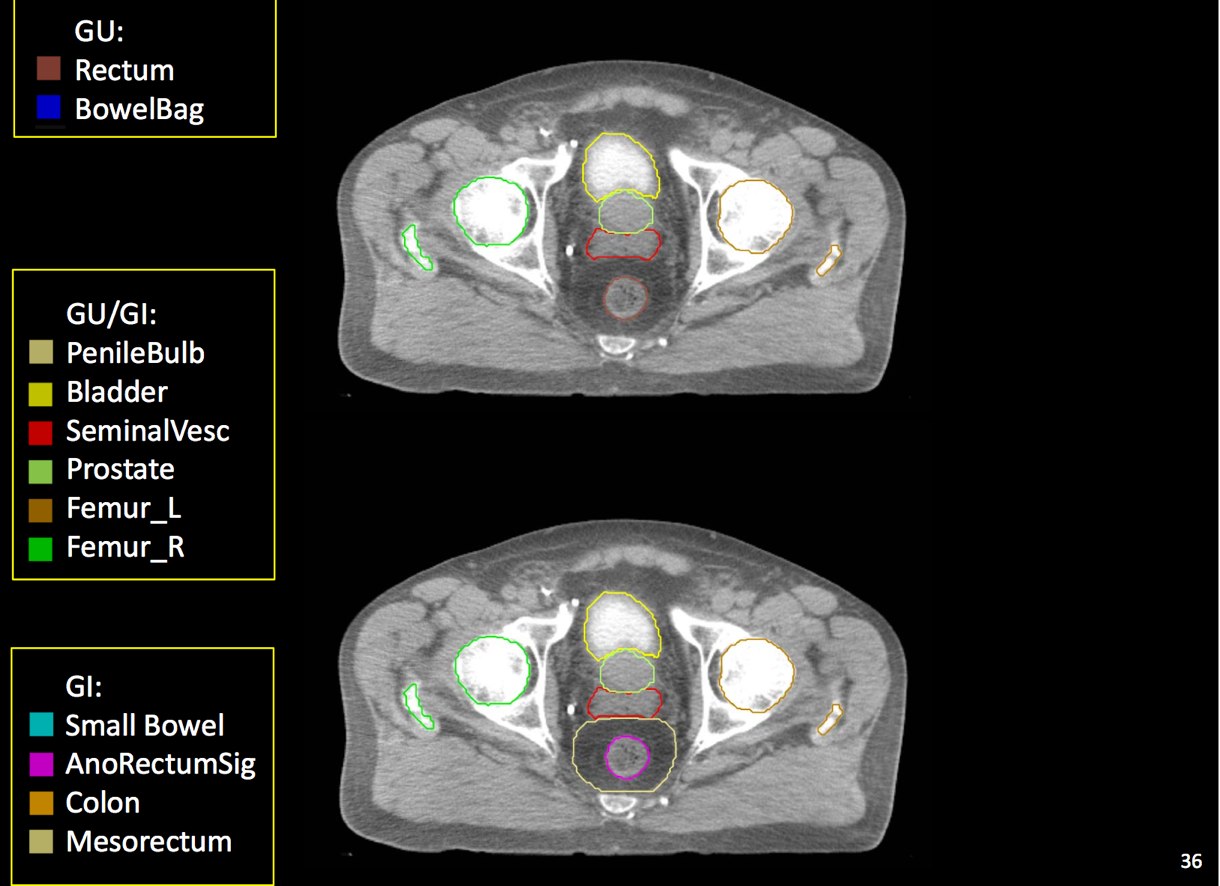

There is significant variation of contours and techniques. The apex and base are regions most susceptable to variation. 3D perspectives help signficantly reduce this variation using transverse, sagital and coronal projections to determine the true extent of the prostate. More recently contouring atlases have been developed by the RTOG with grant assistance from the NCI and are available here. The following images are obtained from the RTOG contour atlases as an excerpt demonstrating areas of potential uncertainty.

There are recent efforts to standardize segmentation names for radiotherapy treatment planning. This is encouraged to allow for inter-institution comparisons, particularly on protocol patients, but it may also assist institutions in comparing dosimetry should additional radiotherapy or other dose questions arise. The normal clinical structures to be identified are: